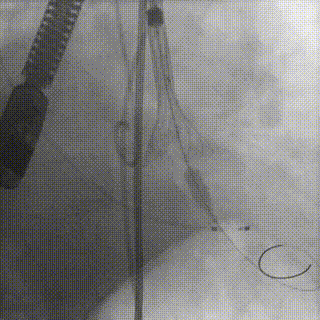

直头导丝跨瓣

球囊预扩